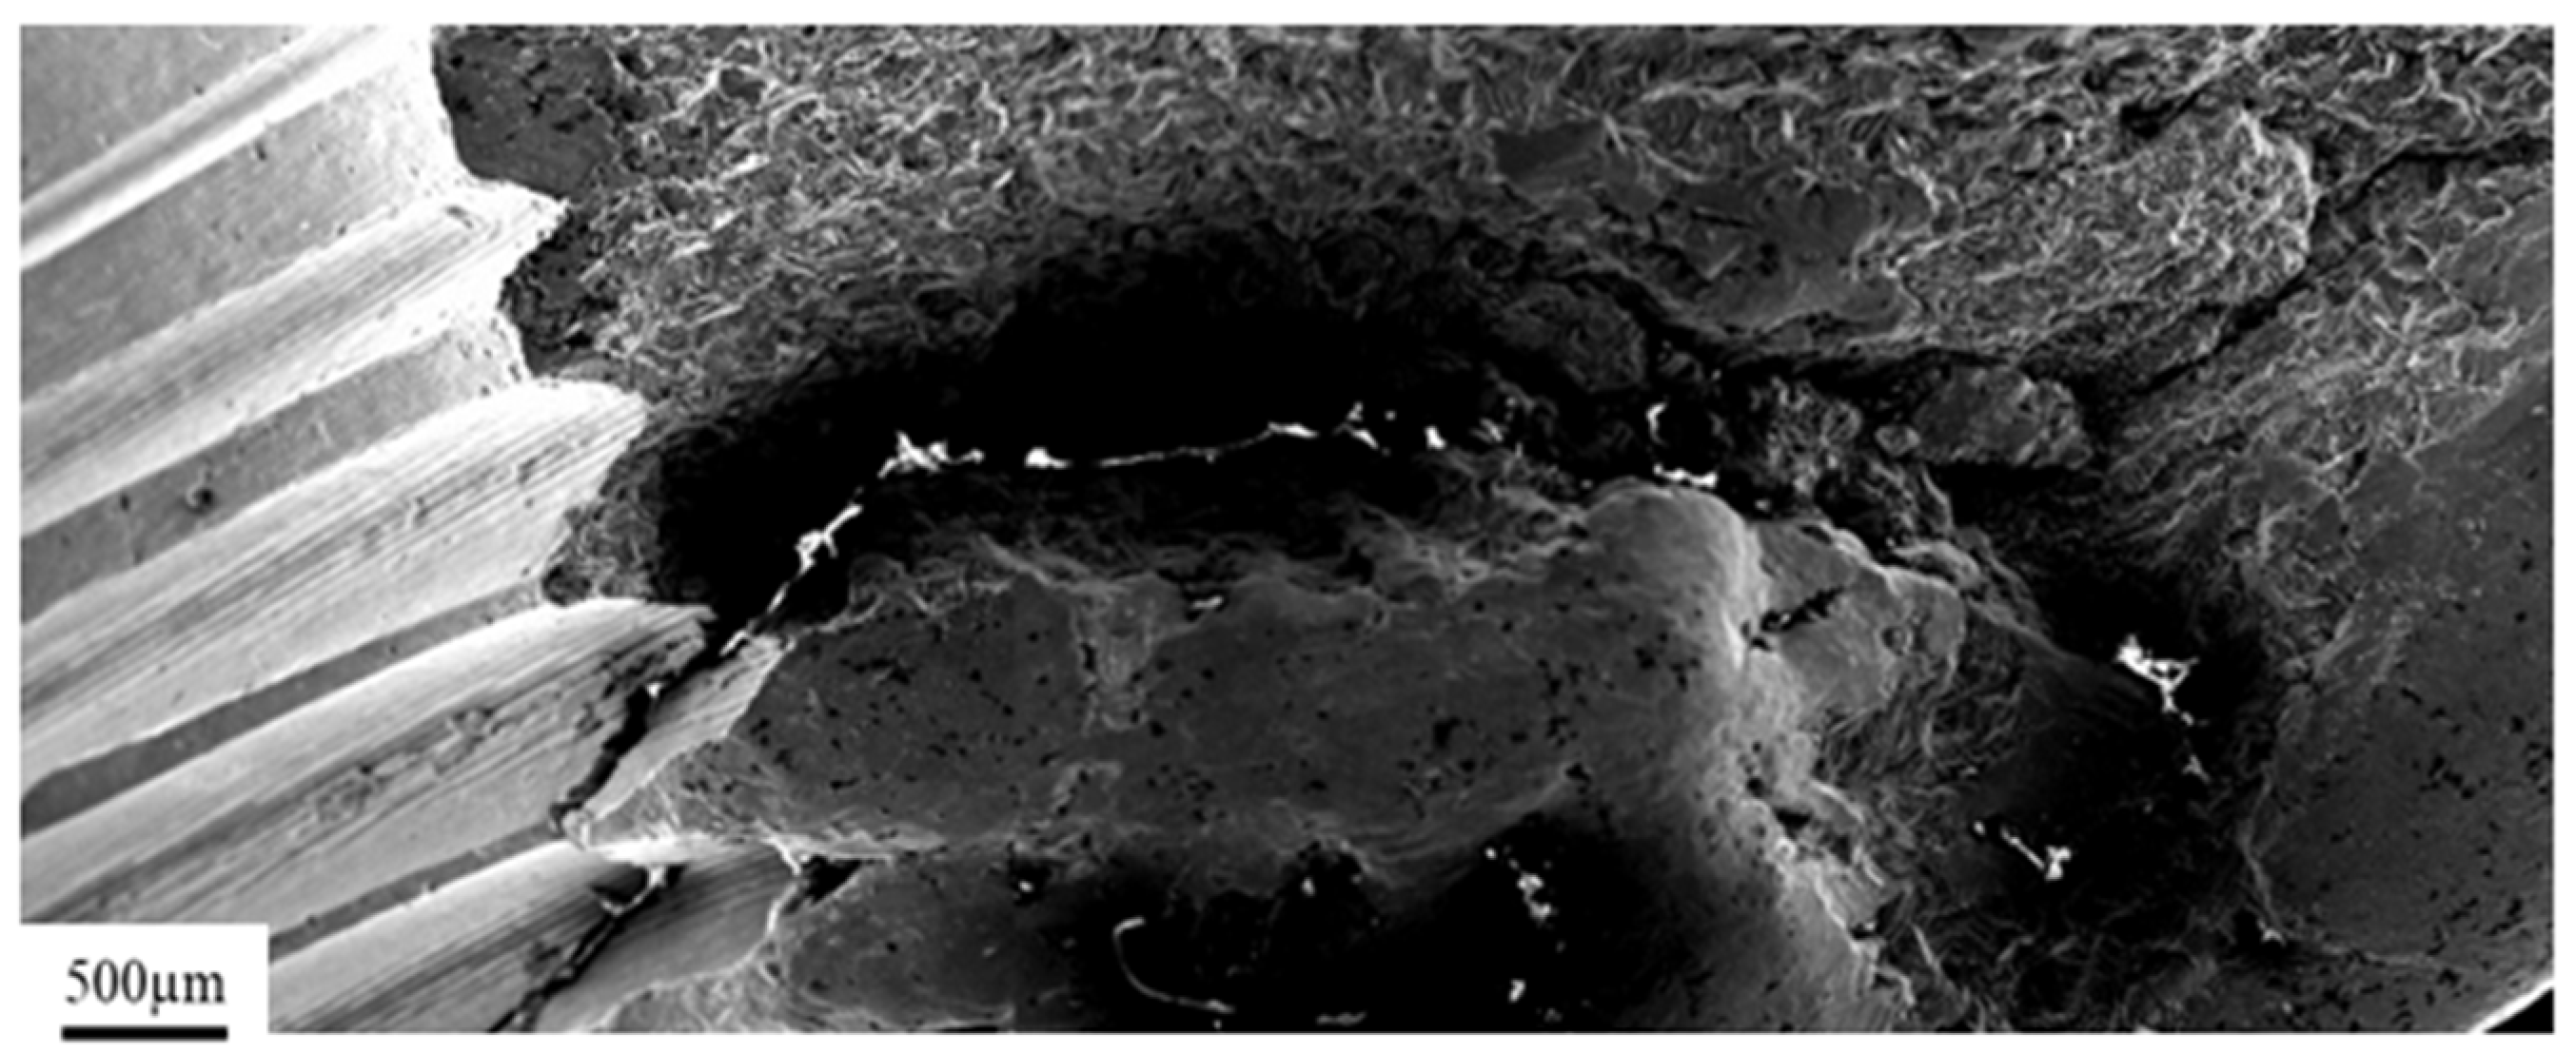

3. Results and Discussion

3.1. Pure Titanium Plates

3.2. Pure Titanium Femoral Implant

3.3. Ti-6Al-4V Titanium Alloy

3.4. X2CrNiMo18-14-3 Steel Femoral Implant